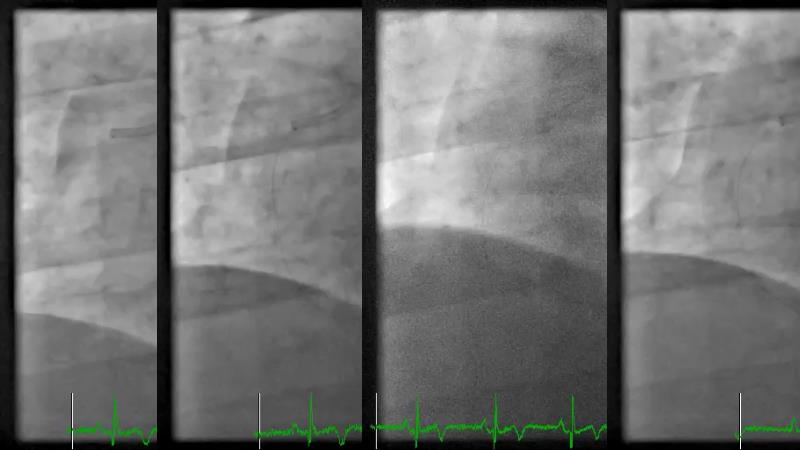

Tune into this 2024 session for insights into the latest ESC guidelines, strategies to prevent and treat no reflow, and an examination of trials like TASTE, TAPAS, and TOTAL on coronary thrombus management. Explore also the outcomes of the CHEETAH study, pondering a potential paradigm shift, and delve into a case study on thrombus removal in a patient with high thrombus burden.